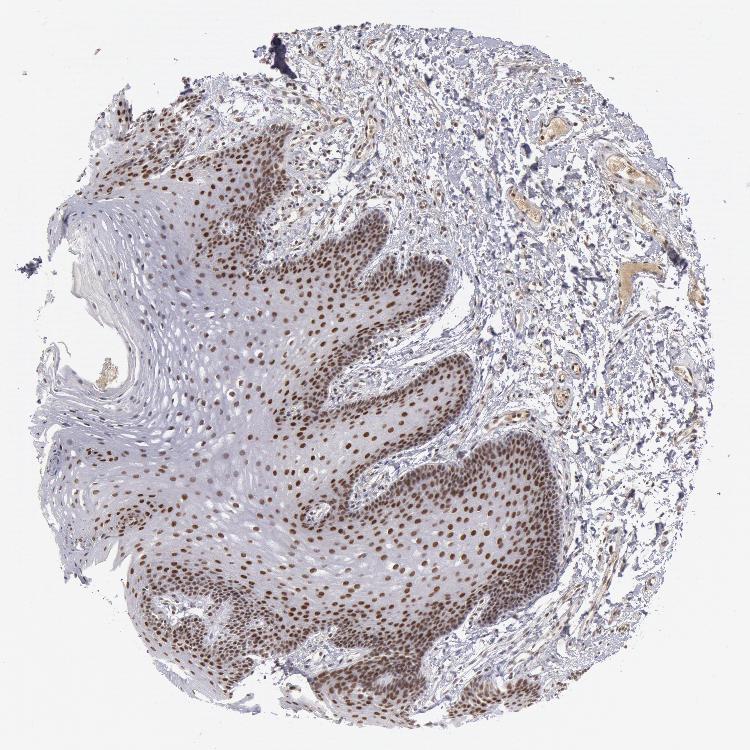

TISSUE PRIMARY DATA ORAL MUCOSA Show tissue menu

Oral mucosa

ORAL MUCOSA - Antibody stainingi

Antibody staining in the annotated cell types in the current human tissue is reported as not detected, low, medium, or high, based on conventional immunohistochemistry profiling in selected tissues. This score is based on the combination of the staining intensity and fraction of stained cells.

Each image is clickable and will lead to virtual microscopy that enables deeper exploration of all samples and also displays staining intensity scores, fraction scores and subcellular localization as well as patient and tissue information for each sample.

Antibody HPA001233Antibody CAB017185

Squamous epithelial cells MediumHigh